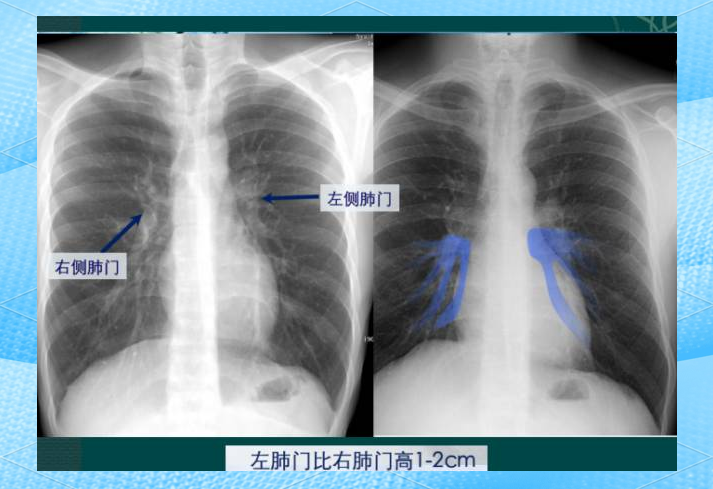

4、心影增大是否有生命危险需具体情况具体分析,不能一概而论其风险程度与病因心功能状态并发症及人群特征密切相关,以下为详细阐述一心影增大的常见原因及一般影响常见病因包括高血压性心脏病长期高血压导致心脏后负荷增加心肌病如扩张型心肌病引发心肌病变瓣膜性心脏病如风湿性;临床以胸片中的心胸比,作为衡量心脏大小的指标心胸比是指心影最大横径,与胸廓最大横径的比值,正常人为05,0506属于轻度心胸比增高,提示心脏心包相关疾病,06以上提示重度心影增大,常见心影横径大的原因如下1心影增大可见于心脏疾病,其中包括扩张型心肌病肥厚型心肌病,或;妊娠中晚期孕妇血容量增加,心脏负担加重,可能出现心影增大一般在分娩后,随着身体恢复,心脏大小会逐渐恢复正常,通常无需特殊治疗,但孕期需密切关注心脏功能和自身症状病理性因素导致的心影增大心肌病如扩张型心肌病肥厚型心肌病等,会导致心肌结构和功能异常,引起心影增大通常需要积极治疗。